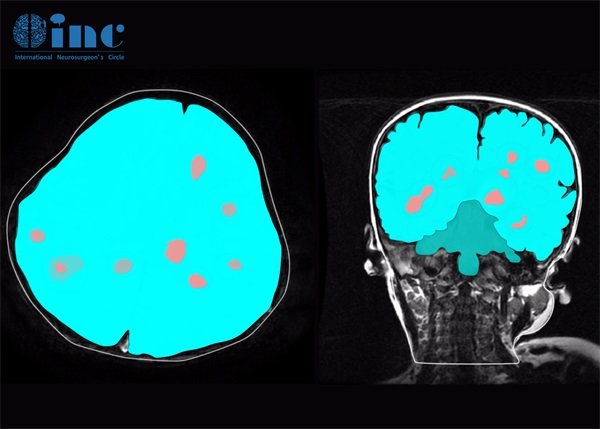

脑部海绵状血管瘤的检查主要依靠影像学技术。常用的检查方法包括:

1. 磁共振成像(MRI)

磁共振成像(MRI)是一种非侵入性检查方法,能够提供高分辨率的脑部图像。对于海绵状血管瘤,MRI图像通常显示为多个信号不均匀的区域,这是由于不同血管成分的影响。

2. 计算机断层扫描(CT)

计算机断层扫描(CT)对于急性出血尤为有用。尽管它的分辨率不如MRI,但在急诊情况下,CT能够快速显示脑内出血、肿胀等情况,帮助医生迅速判断病情。